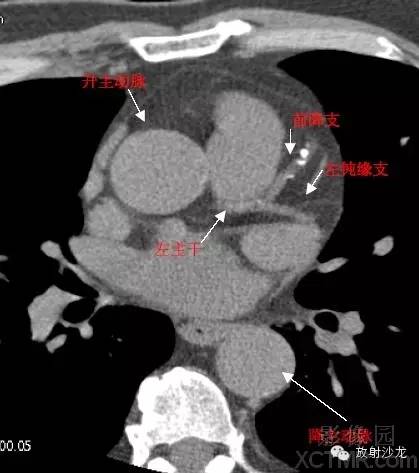

A.Aorta-Ascending Aorta升主动脉

D. Aorta-Descending Aorta降主动脉

LMA -Left Main Artery冠状动脉左主干

LAD -Left Anterior Descending Artery左前降支

LCX -Left Circumflex Artery左回旋支

LMB -Left Obtuse Marginal Branch 左边缘支(钝缘支)